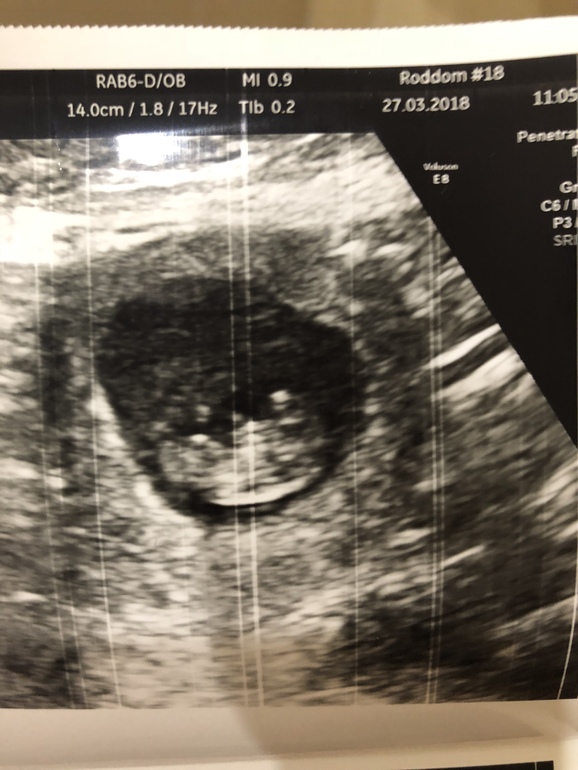

УЗИ, КТГ, доплерЕздили с девчонками в Питер, 27.3 сходила на УЗИ . Все у нас хорошо, человечек дрыгал ножками и ручками :) срок поставили меньше чем по мес. 9+5, плацента по передней стенке . Ну и собственно человек :)